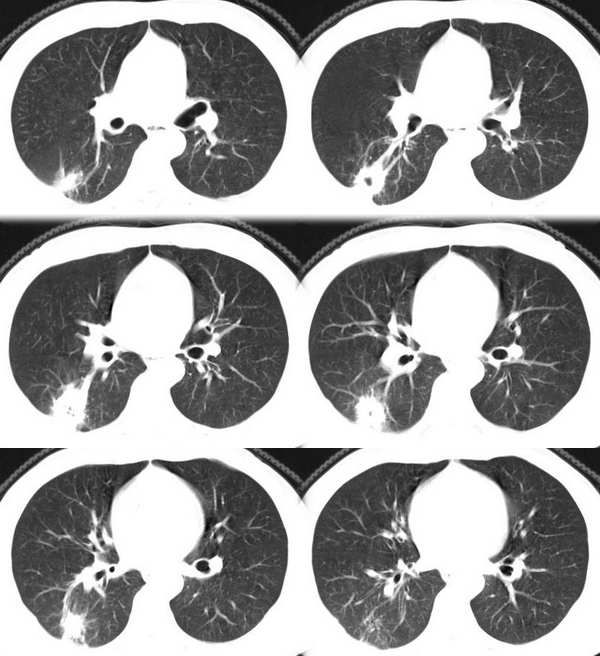

肺癌--腺癌

ct1746 pingfanjun提供 结果右上肺腺癌

76岁;咳嗽、咯血、气短、呼吸困难一年余

ct1847 九目段提供

m/71y,咳嗽咳痰,痰中带血,低热。

ct1962:mzjctmr提供 肺穿病理结果为腺癌

女性,43岁,刺激性干咳4个月,血象血沉正常,无发热

http://www.radida.com/radinet/read.php?tid=7602